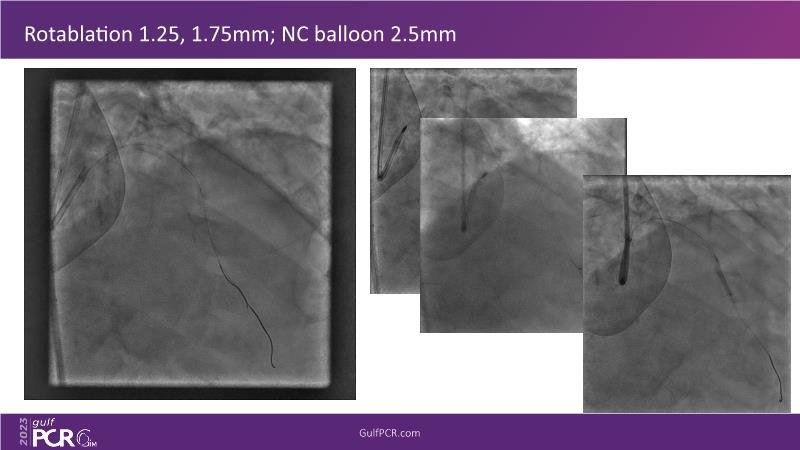

Watch this session to learn all about the intravascular lithotripsy (IVL) mechanism for treating calcified lesions. Discover practical advice and techniques for implementing IVL in challenging calcified lesions and the safe utilization of IVL in left main bifurcations.

- To understand the mechanism of action of intravascular lithotripsy (IVL) for the treatment of calcified lesions

- To uncover practical tips and techniques for intravascular lithotripsy in challenging calcified lesions